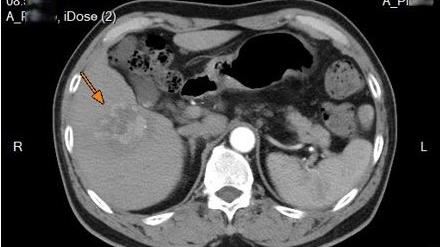

北市聯醫陽明院區胸腔內科醫師蘇一峰在其臉書表示,他日前收治一位胸悶、喘的阿伯,X光看到有10公分大的胸部腫瘤,阿伯的子女希望蘇一峰不要告知阿伯病情,他沉默了5秒,回答「不可能,醫師不能剝奪病人知道病情的權利。」